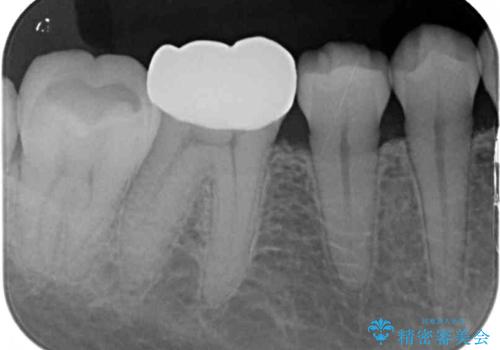

- 左右下顎の奥歯に違和感を感じるとのことで来院された患者様です。

最近ものが挟まりやすくなったり、冷たいものがしみるようになったりと言った症状があり、診査したところ、歯質の欠損や不適修復物などが認められました。

精度の高いセラミックインレーによる修復治療が第一選択となりますが、一方の歯は元々修復物が大きく、咬合力の強い方であったので、セラミッククラウンによる補綴治療を行うこととしました。